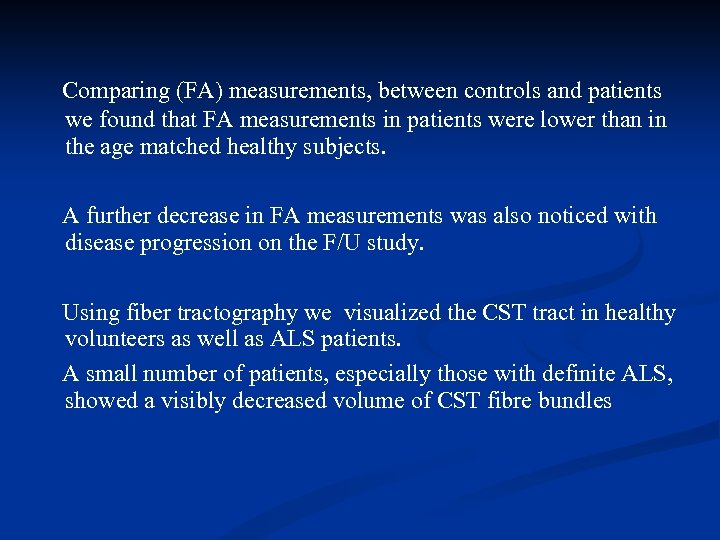

Comparing (FA) measurements, between controls and patients we found that FA measurements in patients were lower than in the age matched healthy subjects. A further decrease in FA measurements was also noticed with disease progression on the F/U study. Using fiber tractography we visualized the CST tract in healthy volunteers as well as ALS patients. A small number of patients, especially those with definite ALS, showed a visibly decreased volume of CST fibre bundles

Comparing (FA) measurements, between controls and patients we found that FA measurements in patients were lower than in the age matched healthy subjects. A further decrease in FA measurements was also noticed with disease progression on the F/U study. Using fiber tractography we visualized the CST tract in healthy volunteers as well as ALS patients. A small number of patients, especially those with definite ALS, showed a visibly decreased volume of CST fibre bundles